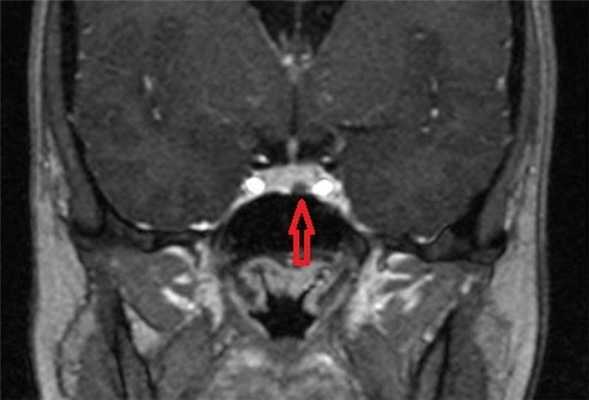

МРТ гипофиза с контрастом. После введения контрастного вещества в гипофизе происходит его накопления и он выглядит светлым. Только участок опухоли не накапливает контрастное вещество и выглятит темным (стрелка).

Для лучшей визуализации микроаденомы применяют динамическое контрастирование. Метод подразумевает использование короткого временного промежутка, когда велика разница сигналов между новообразованием и участками с нормальной структурой. На снимках МРТ с динамическим усилением аденома гипофиза в первой фазе исследования выглядит как гипоинтенсивный очаг на фоне умеренно контрастирующих здоровых тканей железы.